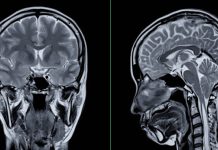

Lecanemab is an investigational anti-amyloid beta protofibril antibody used to treat mild cognitive impairment that occurs due to Alzheimer’s disease and early Alzheimer’s disease with amyloid pathology in the brain.

The efficacy of the drug was based on endpoints of a change in score on the Clinical Dementia Rating–Sum of Boxes (CDR-SB) from baseline, and a change in amyloid burden as shown by positron-emission tomography (PET).